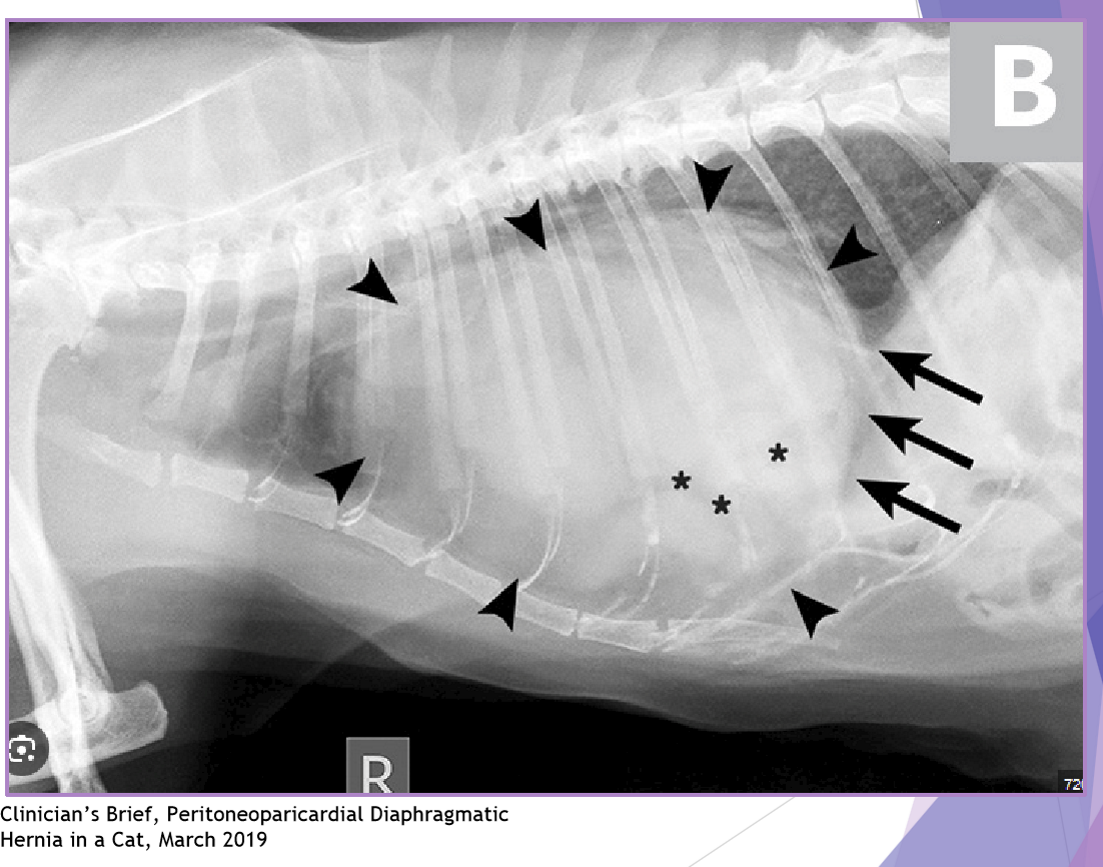

Diaphragmatic hernia - Congenital

Peritoneopericardia d. hernia (PPDH)

congenital common cavity between pericardium and peritoneal cavity

breeds: cocker spaniel, weimaraner, himalayan, DLH

clinical signs:

asymptomatic - most common

respiratory dyspnea

look for other congenital defects

diagnostic evaluation: thoracic radiographs

enlarged, globoid cardiac silhouette

± gas opacity in the cardiac silhouette

pericardial effusion